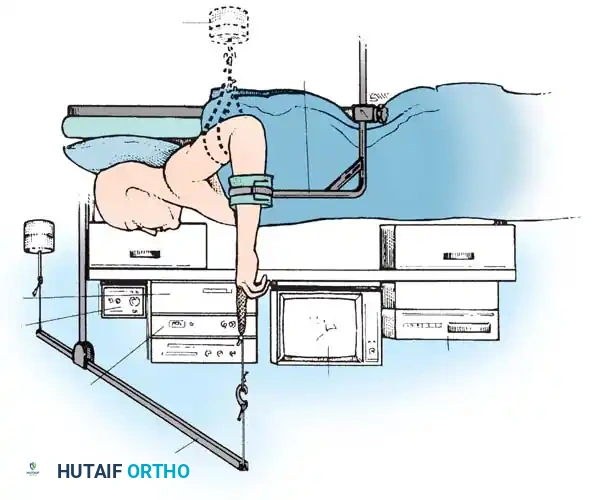

Meticulous patient positioning is the foundation of a successful procedure. Wrist arthroscopy is typically performed under regional anesthesia (brachial plexus block) or general anesthesia, depending on the anticipated duration and the need for concurrent procedures (e.g., bone grafting).

Step-by-Step Positioning

- Patient Orientation: Place the patient supine on the operating table. The operative arm is abducted and placed on a radiolucent hand table.

- Tourniquet Application: Apply a well-padded pneumatic tourniquet to the proximal arm. While optional for simple diagnostic procedures, it is highly recommended for therapeutic interventions and fracture management to ensure a bloodless field.

- Traction Setup: Suspend the hand using sterile finger-traps applied to the index and long fingers (and occasionally the thumb).

- Distraction: Apply 5 to 10 lbs (2.2 to 4.5 kg) of longitudinal traction. This can be achieved via an overhead pulley system with counterweights or a dedicated robotic/mechanical traction tower.

- Joint Angulation: Maintain the elbow in 90 degrees of flexion to neutralize the deforming forces of the forearm musculature. The wrist should be in neutral to slight flexion (10-20 degrees) to open the dorsal radiocarpal space.

- Alternative Position: The horizontal position (elbow extended, forearm pronated on the hand table with longitudinal traction) may be utilized, particularly when arthroscopy is combined with volar plating of distal radius fractures.

🚨 Surgical Warning: Traction Complications

Excessive traction weight (>10 lbs) or prolonged traction time (>2 hours) significantly increases the risk of neurapraxia, skin sloughing at the finger-traps, and postoperative joint stiffness. Always use the minimum weight necessary to achieve adequate joint distraction.